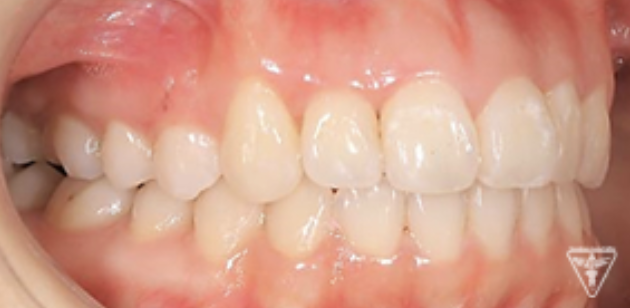

治療前